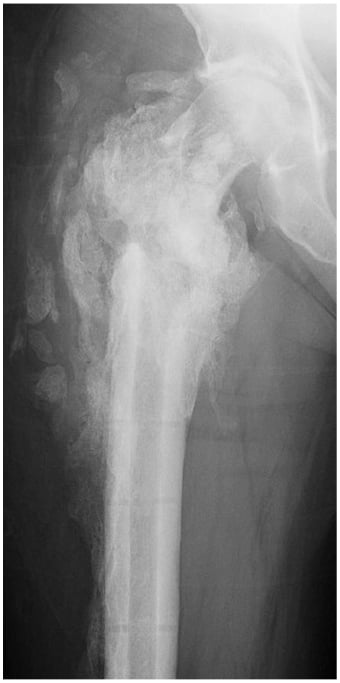

A 62-year-old man sustained a ground-level fall resulting in a right intertrochanteric femur fracture in June 2020. He was overweight (body mass index of 26.55) and his prior medical history included asthma requiring intubation, hypertension, type 2 diabetes, vertebral osteomyelitis/epidural abscess, and pulmonary embolus. He underwent operative fixation at another hospital shortly after injury (Fig. 1). His postoperative course was complicated by infection requiring operative debridement 2 months later. On postoperative day 1, against medical advice, the patient sought evaluation at another hospital. He was ultimately discharged from that hospital and had follow-up with the primary surgeon.

Figure 1: Plain X-ray of the right hip, the first taken after initial debridement.